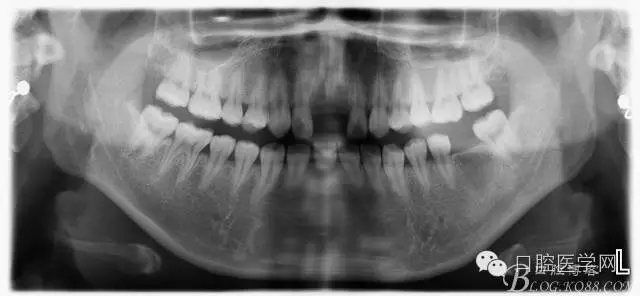

檢查:11.21缺失,笑線高,牙齦較薄,齦乳頭地坪,牙槽骨較飽滿;12.22隱裂,冷熱(一),叩診(一)

術前:該患者因曾受過外傷,造成兩顆中切齒缺失,來院診治。